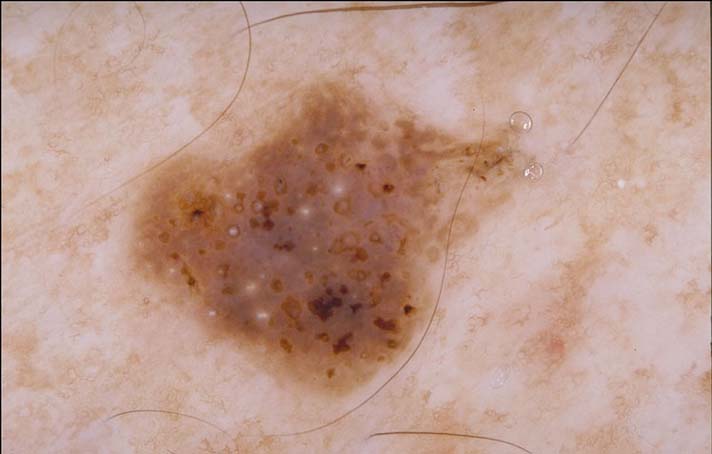

| 150 "diagnosis.char"="Melanocytic lesion" "comment.char"="" "features.char"="Aggregated brown or black globules|Pigment network - pseudonetwork (see exception 1)" | "diagnosis.char"="Invasive melanoma, Breslow 0.3mm" "breslow_depth.float"="0.3" "comment.char"="Note the irregular negative pigment network." "features.char"="Blue-white veil|Multiple (5-6) colors|Scar-like depigmentation" |  |  |